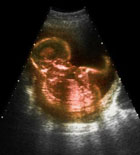

孕期B超

什么是孕期B超

B超是产前检查的一个项目,主要是为了监测胎儿是否存在严重畸形。如体表畸形、内脏畸形等,但并不是每一个都能发现;怀孕早期B超以测量妊娠囊、顶臀长,可以以此确定预产期,和排除异位妊娠;妊娠中晚期测量双顶径、腹围及股骨长度,可了解胎儿的生长发育情况;确定胎儿的位置,区分是头位还是臀位,以及确定胎盘的位置及成熟度;确定胎儿个数,了解羊水量以及测量S/D值,观察胎心是否正常。